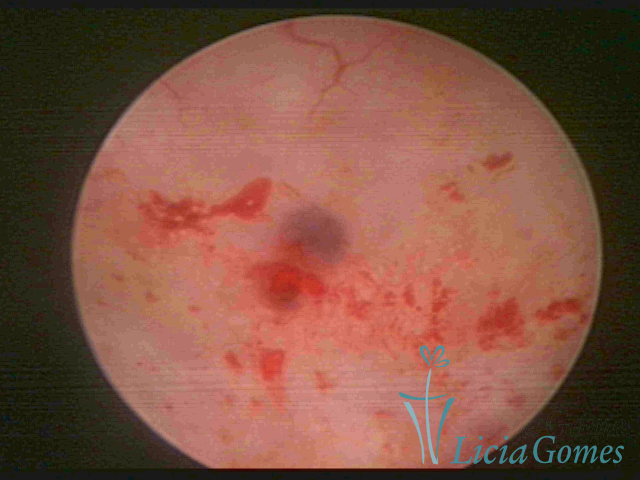

ADENOMIOSE

É a presença de tecido endometrial na camada muscular do útero

A vídeo-histeroscopia permite diagnosticar às lesões próximas às camadas miometriais superficiais, próximo ao endométrio visualizando lesões de coloração violácea, circunscritas, ou acastanhadas com conteúdo achocolatado.